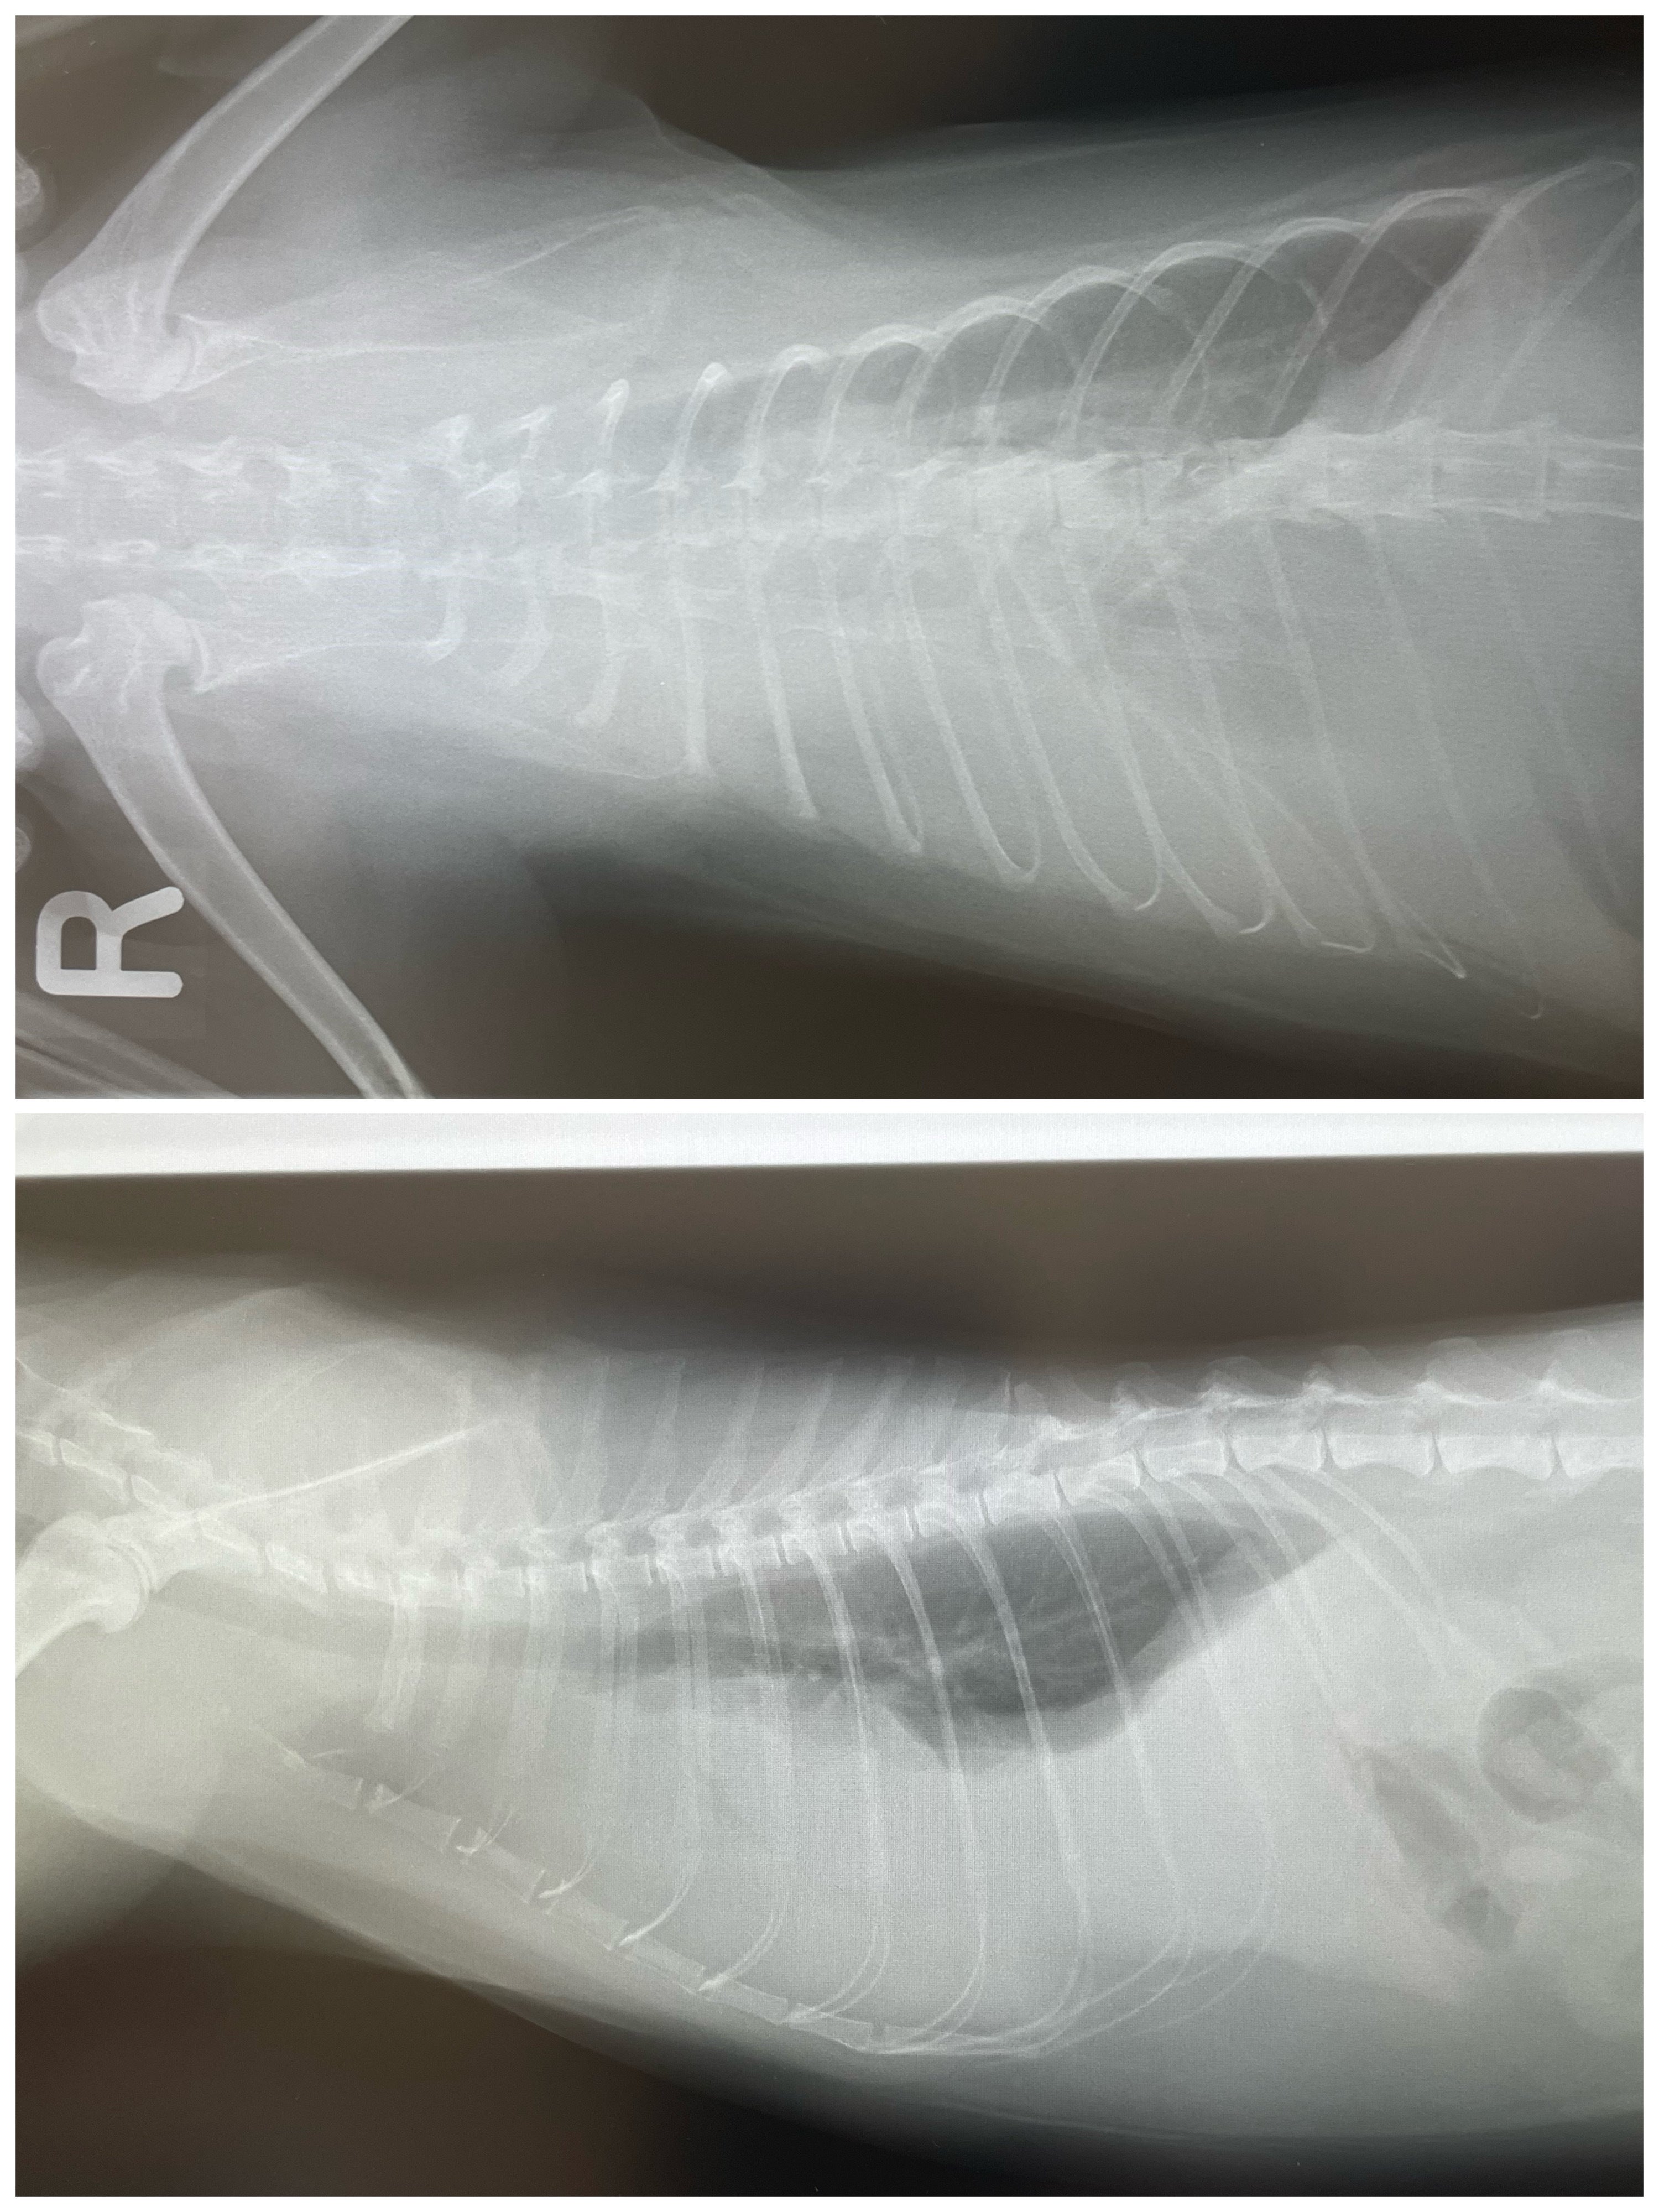

尿路結石で入院した子もきちんと治療し、元気に退院しています。この時の医療費は18万円でした。

肺に膿が溜まり2週間入院した子も居ます。その時は45万円掛かりました。